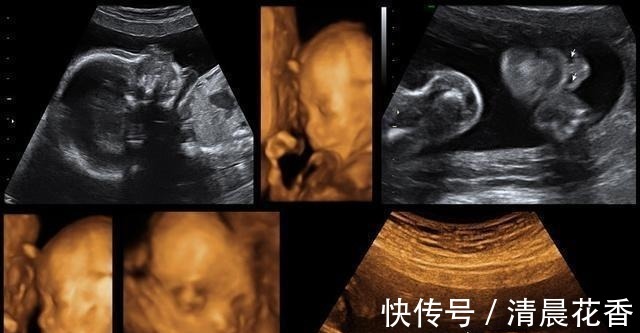

在怀孕之后那么四维大排畸检查是整个孕期非常重要的一个检查项目,在怀孕20周到18周的时候,除了能够筛查一些比较显著的畸形外,还能够看到宝宝人生中第1张照片,但我在做四维的时候妈妈是很激动的,有的妈妈在做四维的时候一次就成功了,那么有的宝宝可能就会不配合,就做了好几遍。

为什么宝宝做四维的时候不愿意动呢?宝宝处于睡眠时间,其实宝宝的生物钟和大人也会处于一个不同的状态,如果是在做四维的时候,宝宝正在睡觉的时间,那么也就会不愿意动了。宝宝性格比较安静,其实我有一个闺蜜的宝宝在整个孕期也是不爱动的,然后胎动也不多,他就非常的害怕,就及时的去做了,产检也是很正常的,可能是胎动比较轻微,自己也并不是非常的敏感,所以说你就会感觉不到。宝宝比较害羞,毕竟这一次是和爸爸妈妈的,第1次见面,宝宝也就没有做好准备,可能就会比较害羞一些,那么宝宝也就会拿着小手遮住小脸,这样的话医生也就没有办法看清变不了,所以说是需要宝宝动一动才能够看清全貌的。